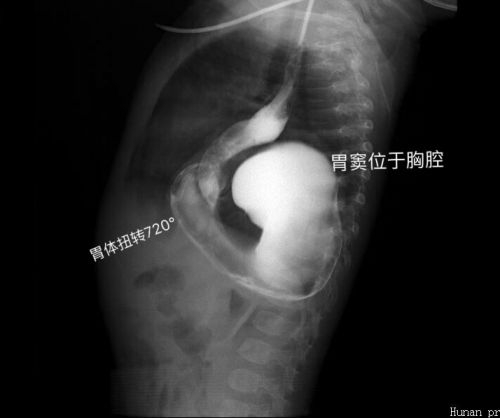

2019年1月19日,9个月大的男婴忱忱(化名)因呕吐4天、加重2天,急诊入住捷克论坛儿童医学中心。忱忱生下来一切正常,生长发育也很好,母乳喂养,6月按时添加辅食。可就在入院前4天,无明显诱因开始出现呕吐食物,并逐渐加重,呕吐咖啡色液体,并解黑色大便1次。入院后考虑为消化道梗阻,经过一系列检查,确诊为:巨大食管裂孔疝并胃扭转。

食管裂孔疝是一种先天性发育异常,较为罕见,表现为膈食管裂孔扩大,膈肌脚薄弱,腹段食管、胃等腹腔内脏器在腹压增高时经食道裂孔进入纵隔,使胃内容物向食管反流,病程较长还可以出现反复呼吸道感染的症状。食道裂孔疝合并消化道梗阻或者反复呼吸道感染的,一般都需手术治疗修复。患儿忱忱不仅全部胃体进入胸腔并且扭转,就连大肠也卡在胸腔,也叫“胸腔胃”,这便是导致忱忱进食后呕吐、不解大便的罪魁祸首。